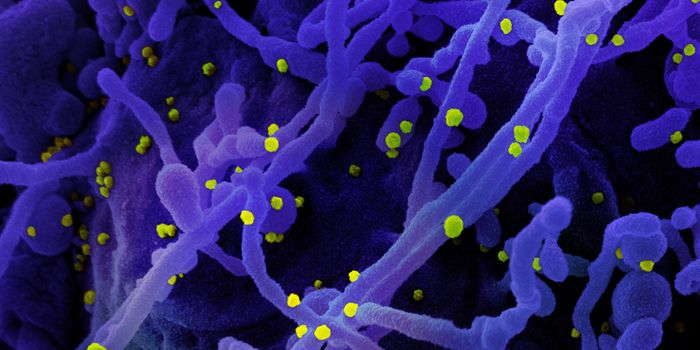

APR 07, 2023MicrobiologyScientists are still learning about SARS-CoV-2, and the illness it causes, COVID-19. While we know a lot about how the v ...